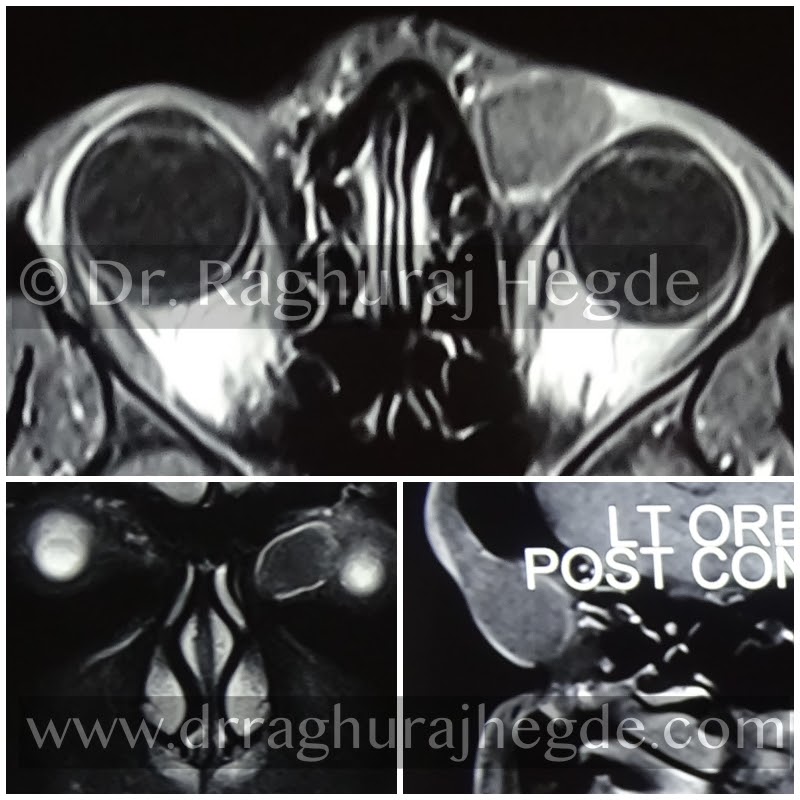

MRI scan showing the entire exent of the tumour.

Given the history, location of the mass and examination, it was clinically diagnosed as dermoid cyst and MRI scan ordered.